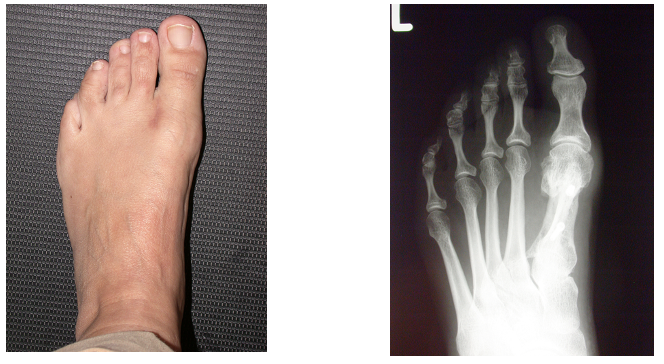

Der gleiche Fuss nach 1 Jahr